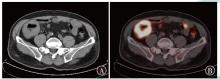

Chen Qiaoliang, Liang Di, Chen Jing, He Jian. Value of 18F-FDG PET/CT in differentiating primary intestinal diffuse large B-cell lymphoma from colon cancer in the ileocecal region[J]. Journal of International Oncology, 2025, 52(10): 628-632.